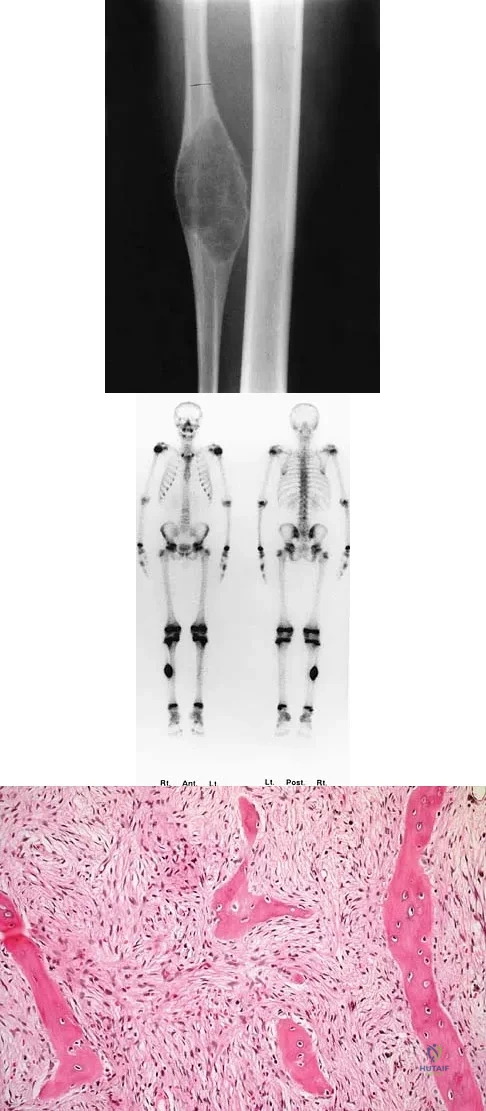

Question 79

A 10-year-old child has leg discomfort with activity. A radiograph, bone scan, and biopsy specimen are shown in Figures 1a through 1c. What is the most likely diagnosis?

Explanation